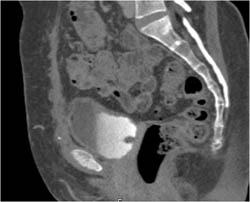

Bladder Cancer